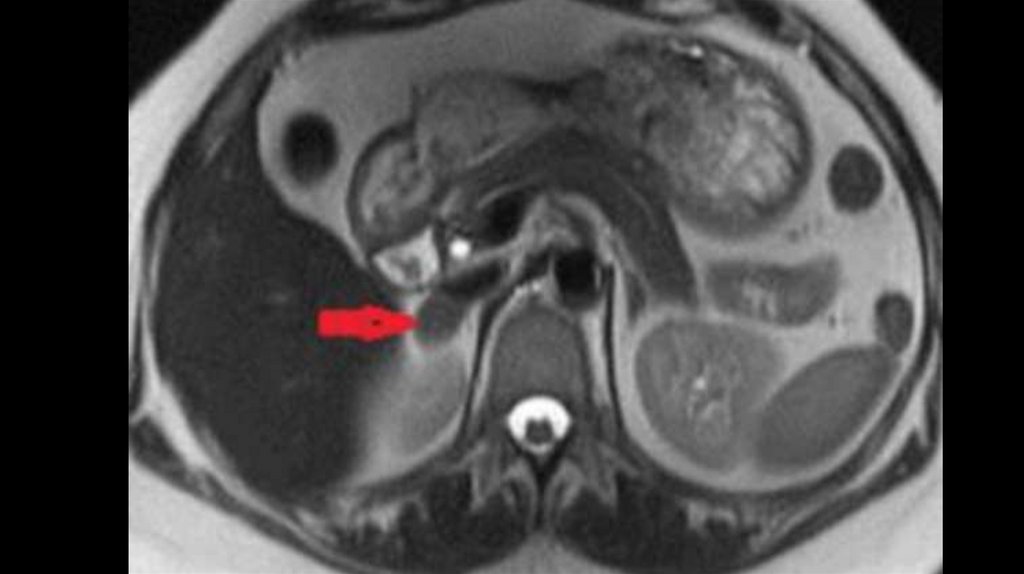

20. МРТ/КТ

• ◊ При МРТ в сочетании с контрастированием гипофиза

(гадолиний) аденома выявляется в 80% случаев.

• ◊ Однако следует иметь в виду, что аденома гипофиза выявляется

у 10% лиц без нарушения функции гипофиза, поэтому

биохимические исследования гормонов имеют решающее

значение.

• ◊ В случае подозрения на АКТГ-независимый синдром Иценко –

Кушинга при МРТ/КТ в надпочечниках можно выявить

характерные морфологические изменения.